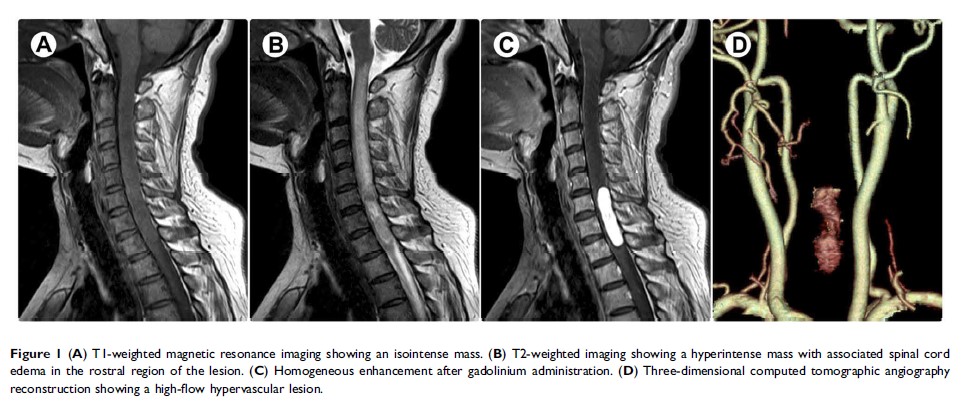

脊髓髓内孤立性纤维性肿瘤:一个罕见而具有挑战性的诊断